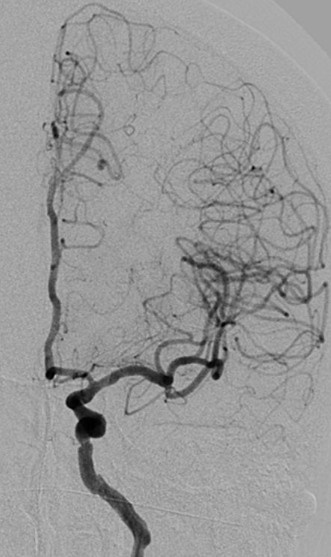

右侧颈动脉造影

左侧颈动脉造影

左侧瘤体形态欠规则,4mm×30mm Streamline 优先处理左侧动脉瘤

术后3月复查,瘤体未见显影,载瘤动脉通畅

同期4mm×20mm Streamline 进一步处理右侧动脉瘤